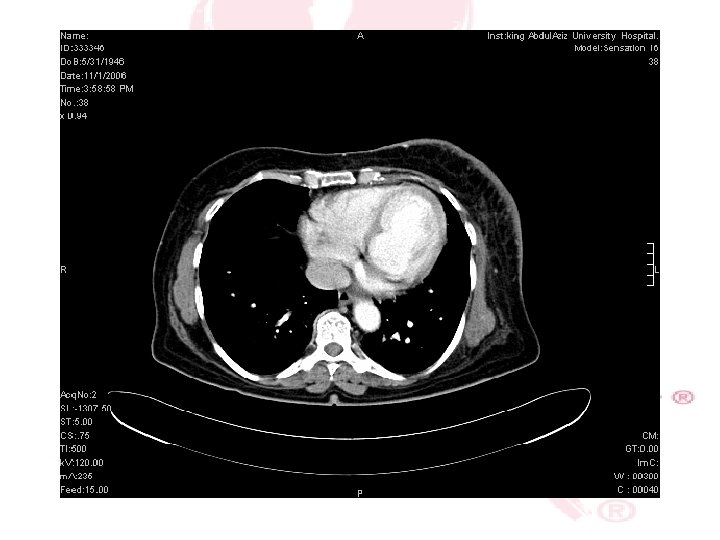

CT SCAN CHEST , ABDOMEN &PELVIS